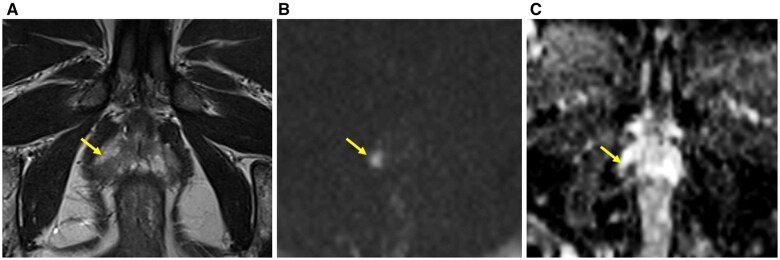

Objectives: The study aims to evaluate Prostate Imaging-Reporting and Data System 4 (PI-RADS 4) lesions, including those with primary diffusion restriction (diffusion-weighted imaging score 4) and those upgraded from PI-RADS 3 due to positive dynamic contrast-enhanced findings, and to compare outcomes between these groups while also assessing cancer detection rates and prostatitis between upgraded cases and PI-RADS 3 lesions.

Methods: In this single-center cohort study, peripheral zone lesions classified as PI-RADS 3 and 4 by multiparametric MRI and biopsied via MRI/transrectal ultrasound-guided targeted biopsy were analyzed.

Conclusions: PI-RADS 3 + 1 lesions show significantly different cancer detection rates from both PI-RADS 3 and 4, suggesting they should be managed as a distinct entity. Higher prevalence of prostatitis in PI-RADS 3 + 1 lesions indicates that clinical evaluation for inflammatory conditions may help reduce unnecessary biopsies in this subgroup.

Advances in knowledge: PI-RADS 3 + 1 lesions show higher cancer detection than PI-RADS 3 but lower than PI-RADS 4, and are more frequently associated with prostatitis than PI-RADS 4. These findings support individualized management to avoid unnecessary biopsies.